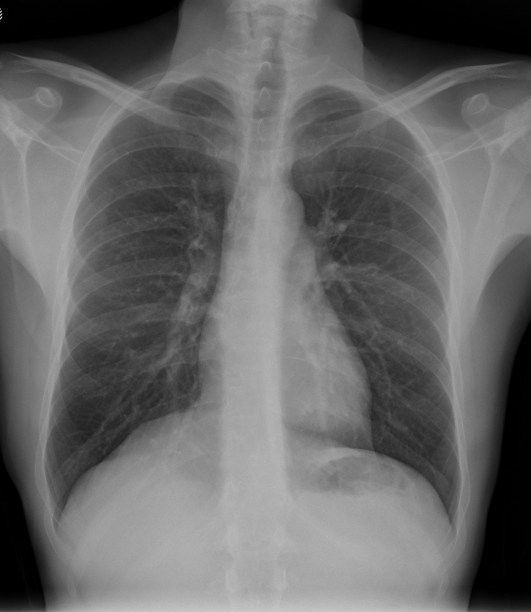

Solución: Es un estudio Normal. Silueta cardiomediastínica y parénquimas pulmonares sin alteraciones significativas.